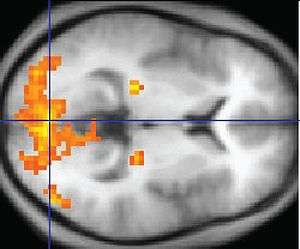

An fMRI image with yellow areas showing increased activity.

Functional magnetic resonance imaging or functional MRI (fMRI) is a functional neuroimaging procedure using MRI technology that measures brain activity by detecting changes associated with blood flow.[1][2] This technique relies on the fact that cerebral blood flow and neuronal activation are coupled. When an area of the brain is in use, blood flow to that region also increases.[3]

Other methods of obtaining contrast are arterial spin labeling[6] and diffusion MRI. The latter procedure is similar to MRI but uses the change in magnetization between oxygen-rich and oxygen-poor blood as its basic measure. This measure is frequently corrupted by noise from various sources and hence statistical procedures are used to extract the underlying signal. The resulting brain activation can be presented graphically by color-coding the strength of activation across the brain or the specific region studied. [7]